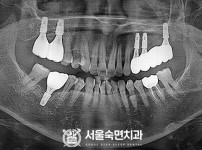

임플란트-전후사진1

임플란트-전후사진2

임플란트-전후사진3

임플란트-전후사진4

치과를-선택할-때-꼭-확인하세요-서울숙면치과-임플란트-전후사진